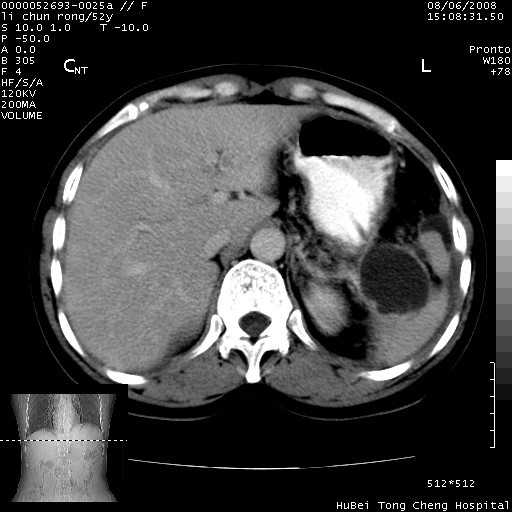

以下是引用云翔在2008-8-7 6:20:00的发言:[br]胰尾部囊性病变,考虑假囊肿,结合实验室检查疾病史

以下是引用zjzjr在2008-8-7 8:38:00的发言:[br]支持胰腺炎伴假囊肿形成,左肾小囊肿.少量腹水.

以下是引用随光逐影在2008-8-7 9:12:00的发言:[br]1)考虑胰腺炎伴假性囊肿形成可能性大;胰腺囊腺瘤待排。2)左肾小囊肿。3)少量腹水。